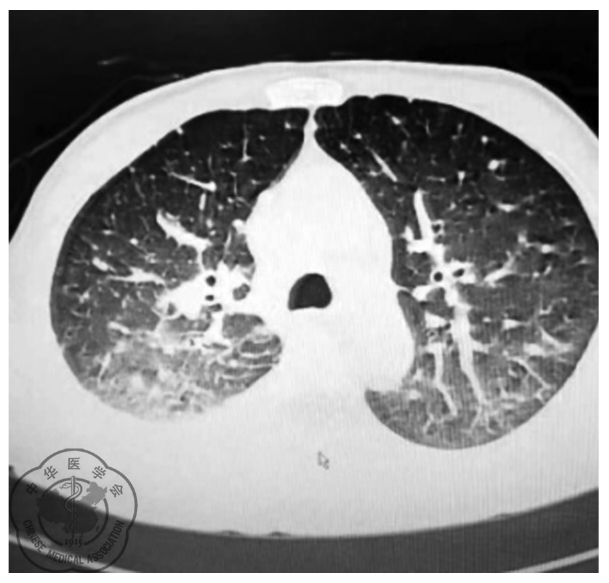

图1 胸部CT示。注:1.双肺多发结节影;2.双肺轻度水肿伴感染;3.纵隔及双侧腋窝淋巴结肿大;4.心包积液,右侧胸腔积液